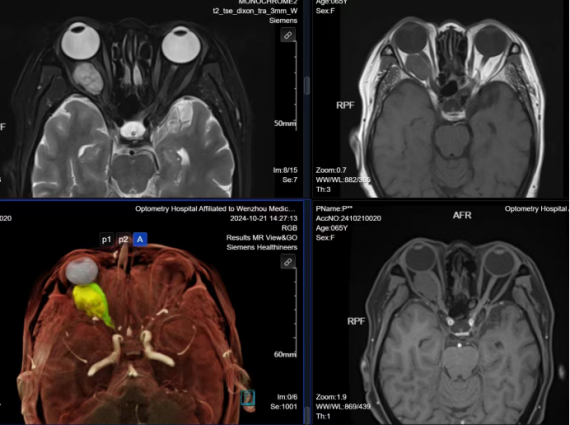

磁共振(MRI),又稱為核磁共振,此“核”是人體內(nèi)的氫原子核,而非核輻射的“核”。磁共振成像檢查是通過將人體放置在強(qiáng)磁場中,利用射頻脈沖(電磁波)對人體內(nèi)氫原子核進(jìn)行激發(fā),產(chǎn)生核磁共振現(xiàn)象,用感應(yīng)線圈采集接受所產(chǎn)生的磁共振信號,進(jìn)而通過計算機(jī)處理而轉(zhuǎn)化為人體可見圖像的一種影像檢查方法。可以說磁共振是我們了解人體解剖和疾病的一種超級影像檢查神器。

磁共振不但沒有電離輻射,而且磁共振檢查還具有多參數(shù)、多序列、多方位成像和軟組織分辨力高等特點(diǎn),具有不用對比劑既可以進(jìn)行MRI血管成像、MRI水成像、MRI功能成像等獨(dú)特的優(yōu)勢。

磁共振可用于全身各部位的檢查,如顱腦、縱隔、乳腺、腹部臟器、盆腔臟器、骨與關(guān)節(jié)、五官及全身軟組織等部位。尤其是對顱腦、脊柱、脊髓、骨關(guān)節(jié)、軟組織等病變檢查更具優(yōu)勢。

溫州醫(yī)科大學(xué)附屬眼視光醫(yī)院影像科率先在溫州市引進(jìn)了全市首臺具有全息仿生功能成像的西門子MAGNETOM Lumina 3T磁共振,該設(shè)備同時采用大孔徑 (70CM)、短磁體(172CM)的人性化設(shè)計,搭載最新智能梯度、功能強(qiáng)大軟件等,與傳統(tǒng)機(jī)型相比,具有更智能、更舒適、更高效、更清晰、更直觀的特點(diǎn),能夠全面滿足眼眶(眼球)、頭部、胸部、腹部、盆腔、脊柱及四肢關(guān)節(jié)等全身各部位的影像檢查需求。